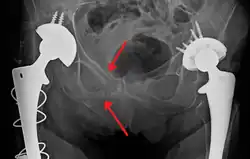

Blunt pelvic trauma

The most common causes of blunt pelvic trauma are motor vehicle crashes and multiple-story falls, and thus pelvic injuries are commonly associated with additional traumatic injuries in other locations.[27] In the pelvis specifically, the structures at risk include the pelvic bones, the proximal femur, major blood vessels such as the iliac arteries, the urinary tract, reproductive organs, and the rectum.[28][27]

.png)

One of the primary concerns is the risk of pelvic fracture, which itself is associated with a myriad of complications including bleeding, damage to the urethra and bladder, and nerve damage.[29] If pelvic trauma is suspected, emergency medical services personnel may place a pelvic binder on patients to stabilize the patient's pelvis and prevent further damage to these structures while patients are transported to a hospital. During the evaluation of trauma patients in an emergency department, the stability of the pelvis is typically assessed by the healthcare provider to determine whether a fracture may have occurred. Providers may then decide to order imaging such as an X-ray or CT scan to detect fractures; however, if there is concern for life-threatening bleeding, patients should receive an X-ray of the pelvis.[30] Following initial treatment of the patient, fractures may need to be treated surgically if significant, while some minor fractures may heal without requiring surgery.[27]

A life-threatening concern is hemorrhage, which may result from damage to the aorta, iliac arteries, or veins in the pelvis. The majority of bleeding due to pelvic trauma is due to injury to the veins.[29] Fluid (often blood) may be detected in the pelvis via ultrasound during the FAST scan that is often performed following traumatic injuries. Should a patient appear hemodynamically unstable in the absence of obvious blood on the FAST scan, there may be concern for bleeding into the retroperitoneal space, known as retroperitoneal hematoma. Stopping the bleeding may require endovascular intervention or surgery, depending on the location and severity.[28]